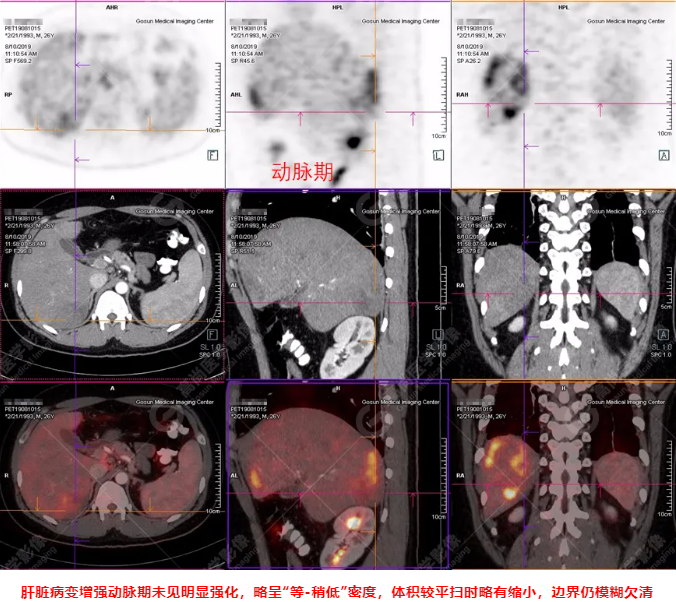

PET/CT全身圖

PET/CT診斷

嗜酸性粒細(xì)胞增多癥肝浸潤(rùn)